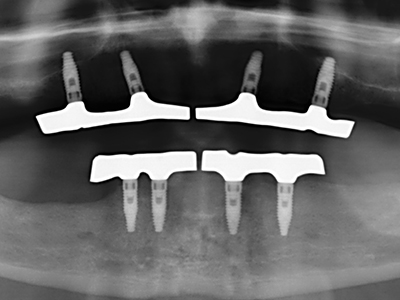

As shown in the past, basically any bone surgery procedure represents a possible indication for piezo surgery. Thus preparation of the mobile segment in distraction osteogenesis (Fig. 23-25) and sandwich osteotomy uses special attachments without endangering the blood supply to the crestal section, which is essential for the success of both techniques (Gonzalez-Garcia, Diniz-Freitas et al. 2008).

For removal of an implant, a vestibular bone cover that is replaced after removal of the implant screw can be prepared to retain the contour of the alveolar ridge.

There are additional applications in sinus surgery. Pathologies and foreign bodies can be removed from the sinus after concentric preparation of a generally trapezoid bone cover in the facial sinus wall. The bone cover is repositioned on conclusion of the intra-antral operation component and secured by wedging or adaptive sutures to prevent dislocation.

Purely orthodontic indications include orthognathic surgery, genioplasty (Fig. 27-30) and orbital decompression in patients with advanced endocrine orbitopathy as a result of Basedow’s disease (Ponto, Zwiener et al. 2014). Piezo devices are also used in maxillofacial surgery and to remove tumours at the base of the skull in various hospitals.